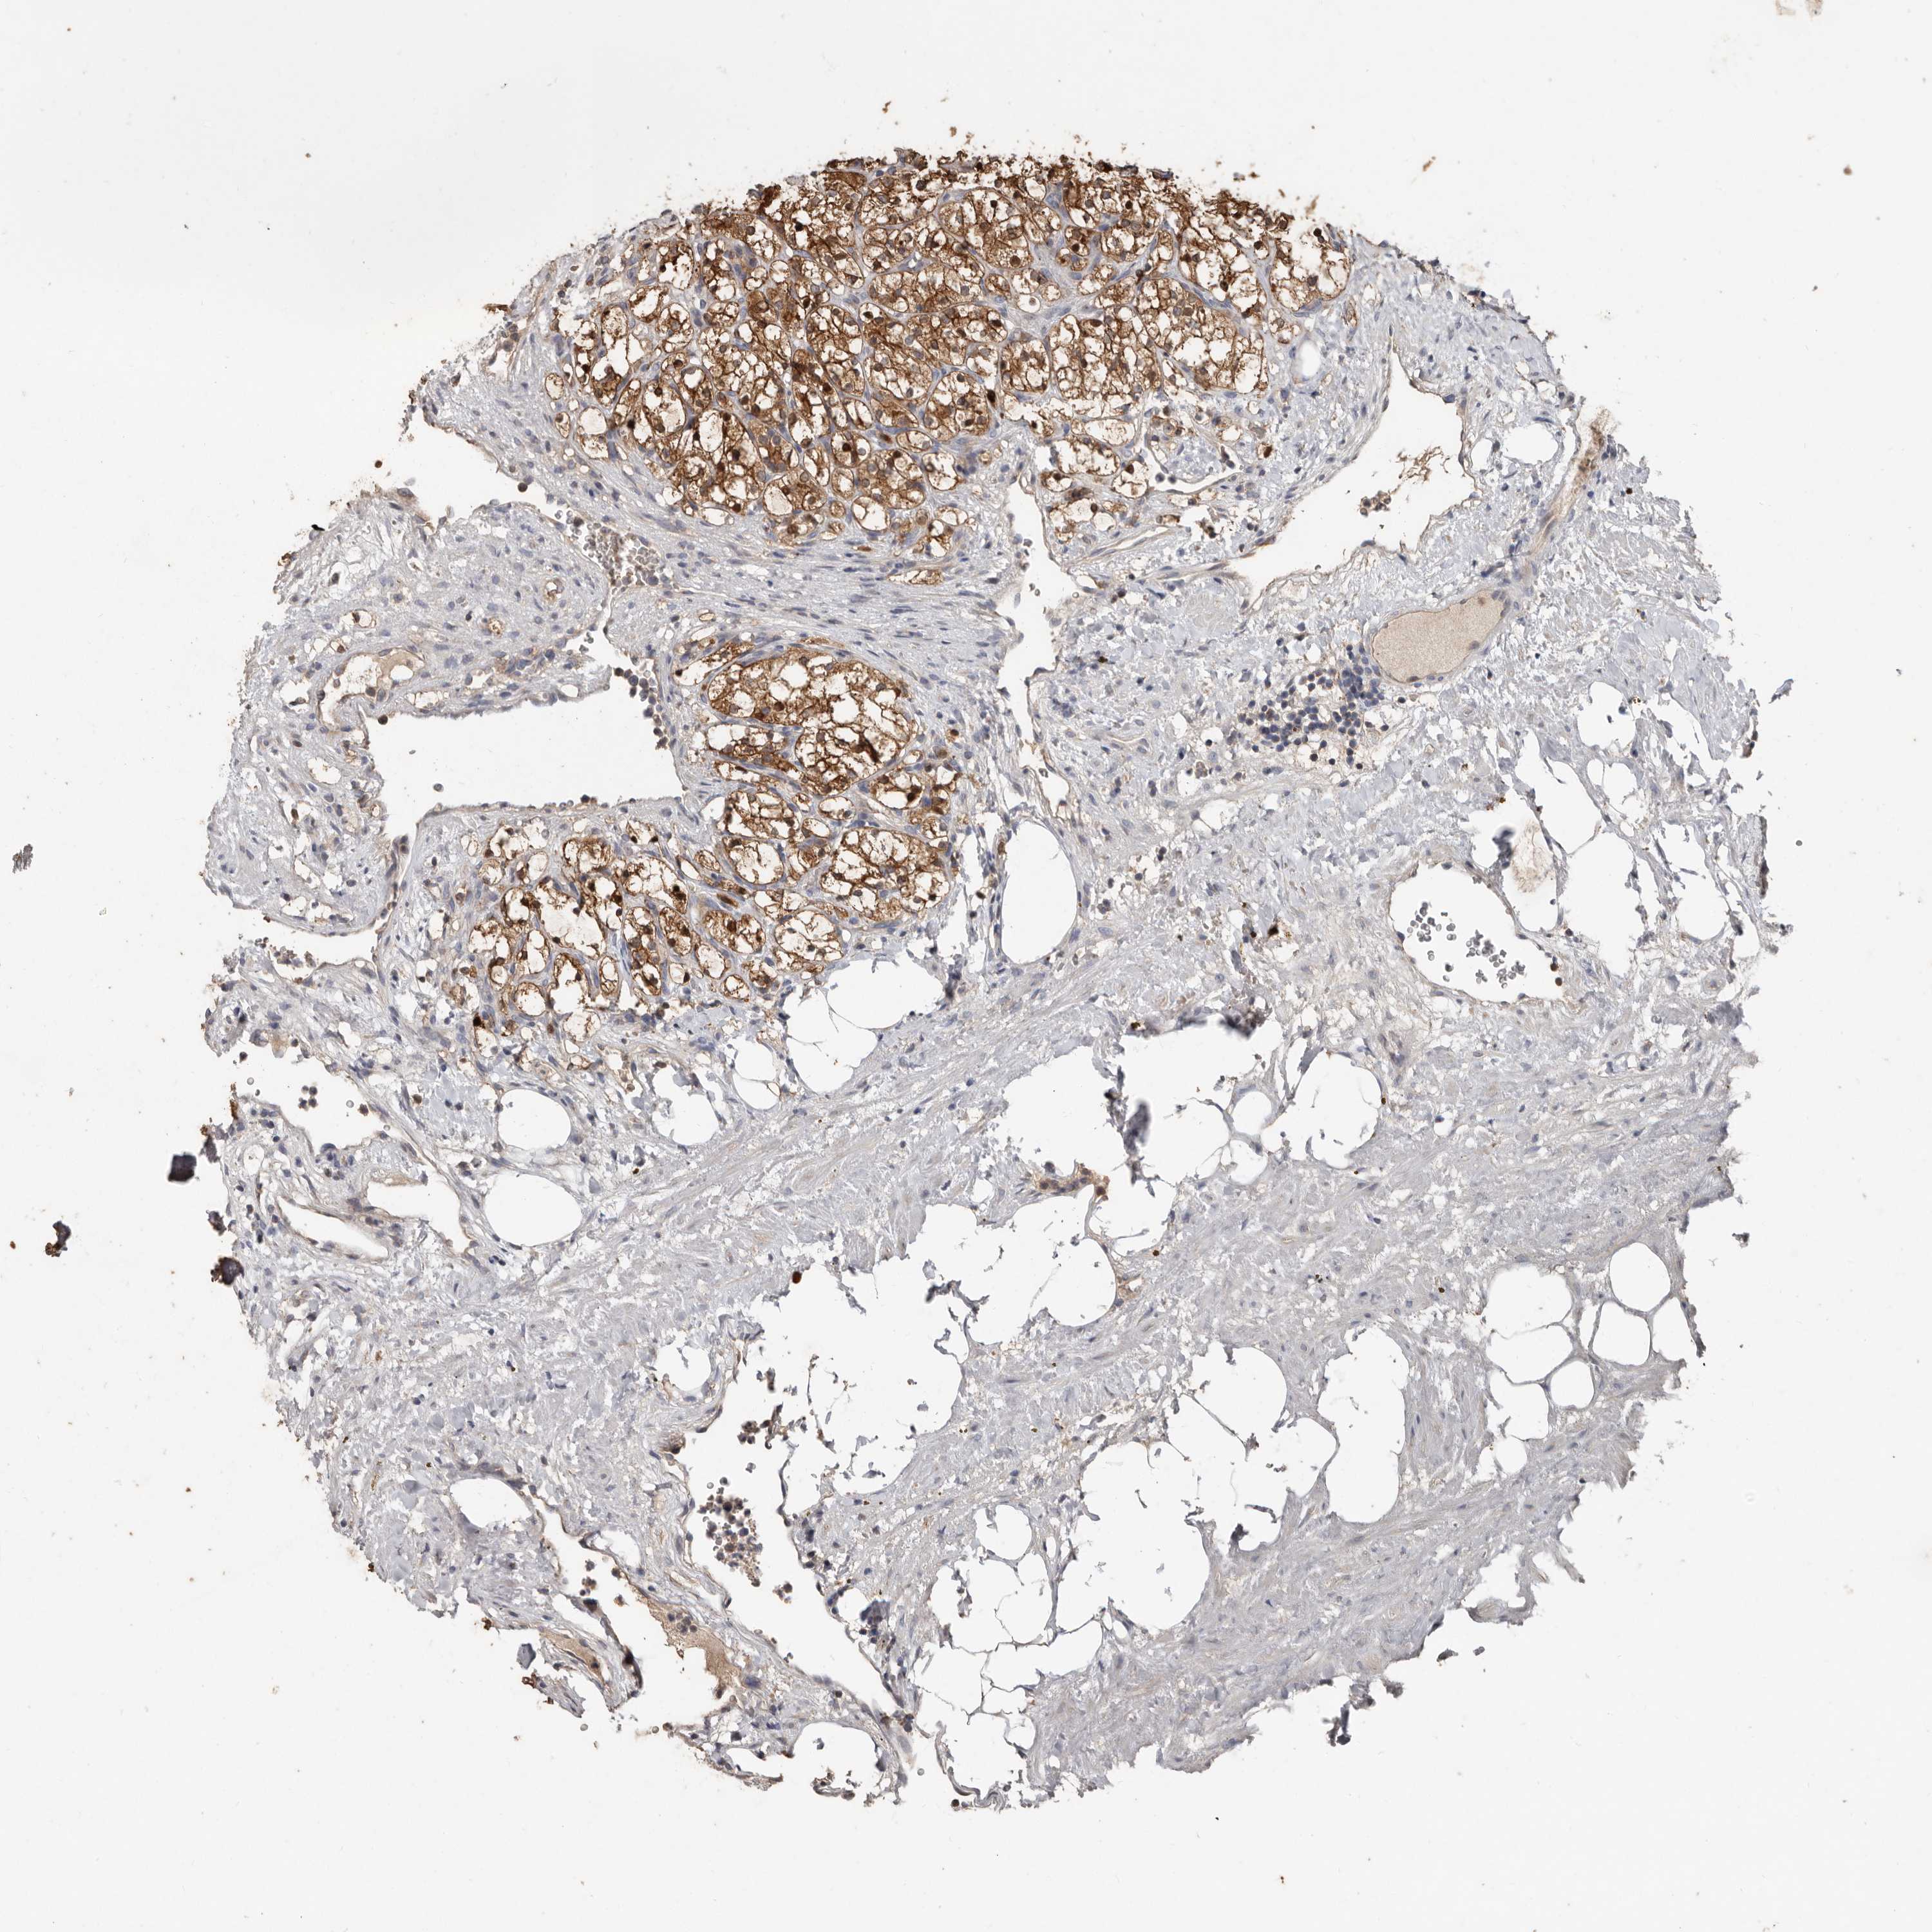

CANCER RENAL CANCER Show tissue menu

KICH TCGA KIRC TCGA KIRC VALIDATION KIRP TCGA PROTEIN RCC CPTAC PROTEIN EXPRESSION